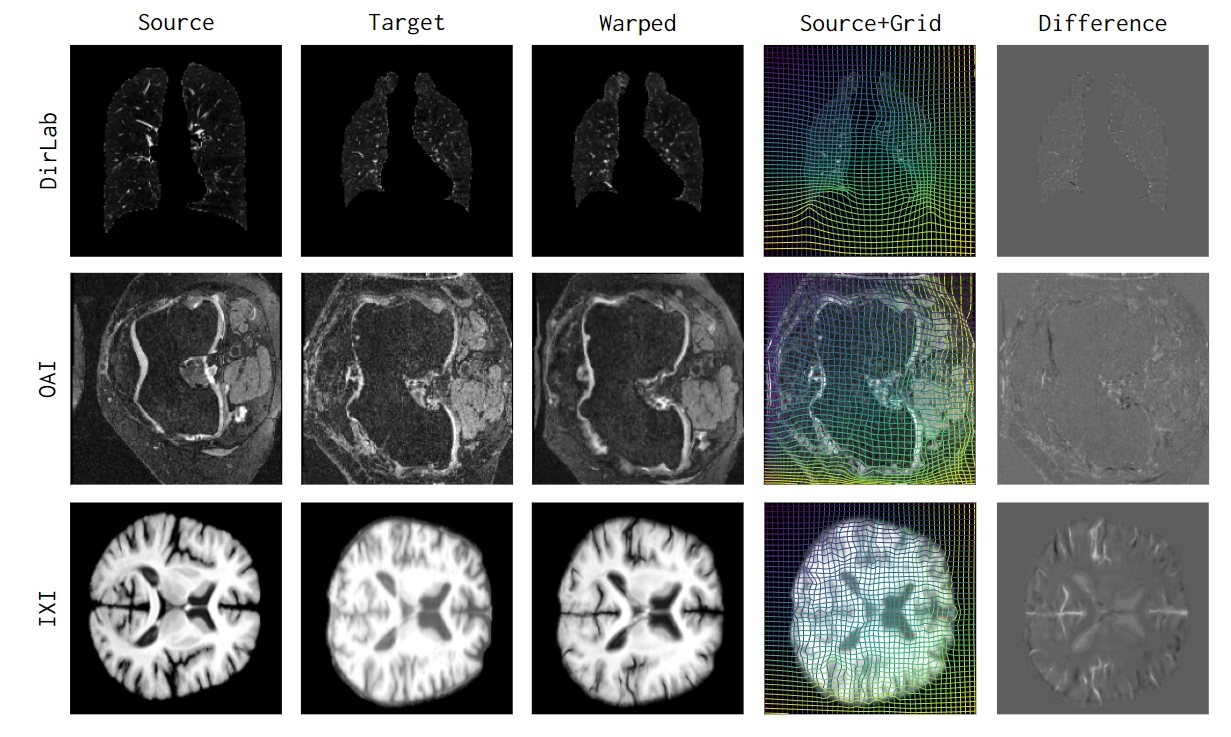

uniGradICON_teaser.png

uniGradICON: A Foundation Model for Medical Image Registration

Lin Tian, Hastings Greer, Roland Kwitt, and 5 more authors

In Medical Image Computing and Computer Assisted Intervention – MICCAI 2024, 2024